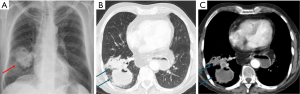

Cavitation within areas of consolidation is a sign of necrotizing pneumonia, often caused by pathogens such as Staphylococcus aureus and Klebsiella pneumoniae. These bacteria are more likely to induce cavitation (Figure 4) (7,8,13). Occasionally, Staphylococcus aureus can occasionally lead to the formation of pneumatoceles, particularly in children (14). Pneumatoceles are thin-walled, cysts that may contain air-fluid levels and typically resolve spontaneously within weeks to a few months (14).

Lung abscesses, a complication of pneumonia, are typically caused by mixed anaerobic infections, with Staphylococcus aureus and Pseudomonas aeruginosa being common culprits (15). Aspiration events are a major risk factor for lung abscesses, with risk factors including alcoholism, poor dental hygiene, impaired consciousness, esophageal motility disorders, and neurological disease (8,15).

In contrast to cavitating pneumonia, which presents with residual consolidation around the cavity, a lung abscess is a more established process, typically showing little to no surrounding consolidation (7). Imaging findings for lung abscesses typically include cavitary lung lesions with or without fluid levels, variable wall thickness (5–15 mm), peripheral contrast enhancement, and a necrotizing center (Figure 5) (7). If the abscess is located peripherally, focal pleural thickening or an empyema may be present (7).